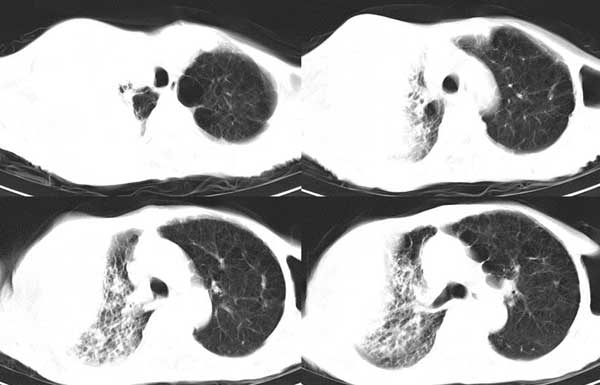

患者男,81岁,咳喘10余年,继往结核病史,发现胸部体表肿物(具体时间不详)就诊

右侧胸廓塌陷。右前上外侧胸壁软组织肿块,其内见有低密度影,肋骨呈溶骨性表现。右肺上叶见大量的间质纤维化表现。右侧膈肌上抬。

患者男,81岁,咳喘10余年,继往结核病史,发现胸部体表肿物

考虑:1、继发性结核,右结核性胸膜炎伴胸壁结核性感染

2、右侧胸壁恶性肿瘤。

肺尖巨大肿块影阴,胸壁受侵肋骨破坏,肿块密度不均且穿破胸壁入皮下,应该是:肺上沟癌;由于肺内有斑片状播散病灶,因此不排除胸壁结核。

患者男,81岁,咳喘10余年,继往结核病史,发现胸部体表肿物。

考虑:1 右侧胸壁恶性肿瘤(多考虑:胸膜间皮瘤)。

2 继发性结核,右结核性胸膜炎伴胸壁结核性感染。